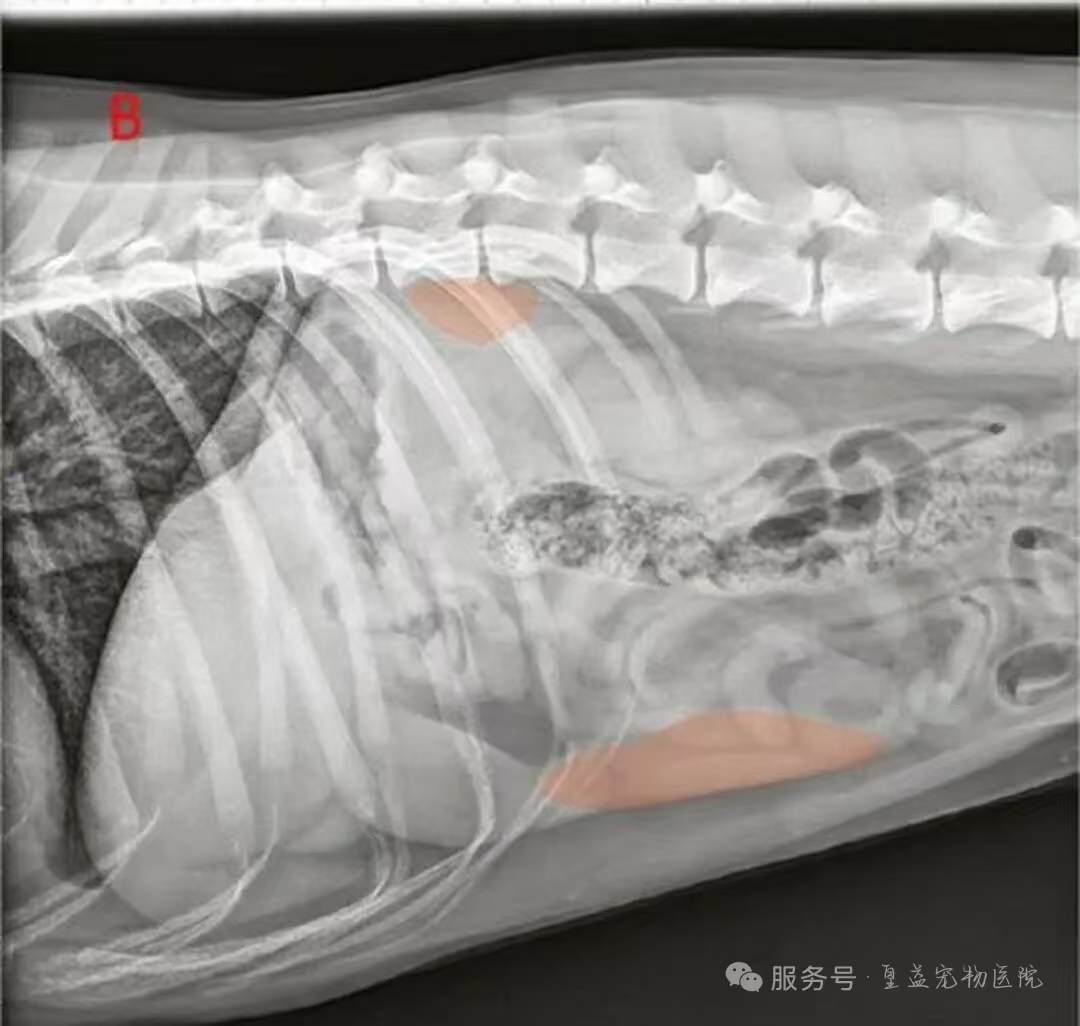

3. X光片:查看肿瘤是否转移到了肺部等其他器官。